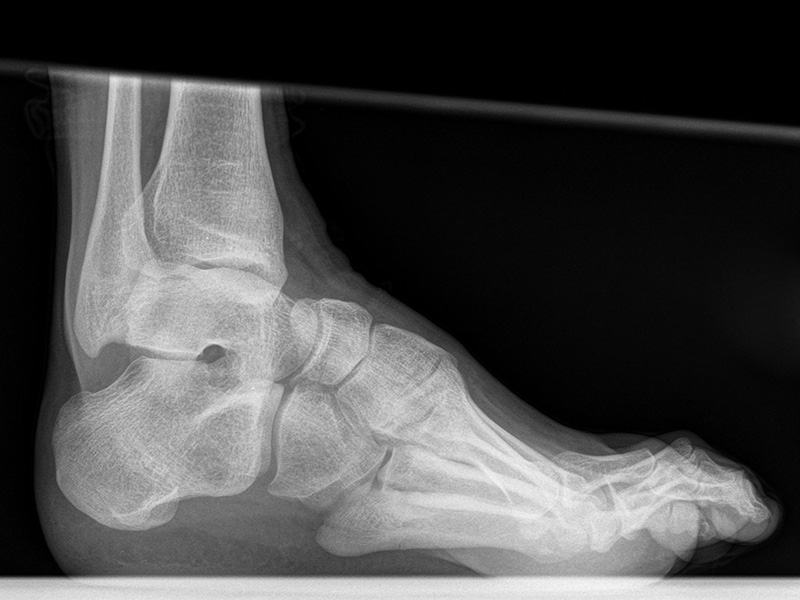

Fuß seitlich mit Belastung

Positionierung:

• Der Patient steht auf beiden Füßen mit gleichmäßiger Lastverteilung.

• Der zur Röntgen der Fuß wird längs des Films positioniert.

• Die Kassette steht senkrecht zum Boden, medial dem Fuß anliegend.

• Der Zentralstrahl wird von lateral nach medial zentriert auf das Kalkaneokuboidalgelenk knapp cranial der Os metatarsale V Basis ausgerichtet.

• Die Röntgenröhre steht 0° horizontal.

Kennzeichen des Röntgenbildes:

• Standardabbildung des Fußes zusammen mit der belasteten d.-p. Aufnahme und der unbelasteten 45° Pronationsaufnahme.

• Überblick über die Fußanatomie und Fußstatik.

• Die seitliche Aufnahme liefert Informationen zur Stabilität des Längsgewölbe und zu den Achsen von Talus, Kalkaneus und Metatarsale I.

• Die Aufnahme wird eingesetzt zur Darstellung von freien Gelenkkörpern sowie knöchernen Veränderungen am Achillessehnenansatz oder der Plantarfaszie.

Besondere Bemerkungen zum Beispielbild:

• Schwere Hallux valgus Deformität.

• Die Sesambeine sind luxiert, ebenso das Großzehengrundgelenk. Luxation des Metatarsophalangealgelenks II.

• Degenerative Veränderungen der tarsometatarsalen (TMT) Gelenkreihe, betont TMT II und III.

Zur Vollansicht und zum Lesen der Bildbeschreibung bitte die Bilder anklicken.